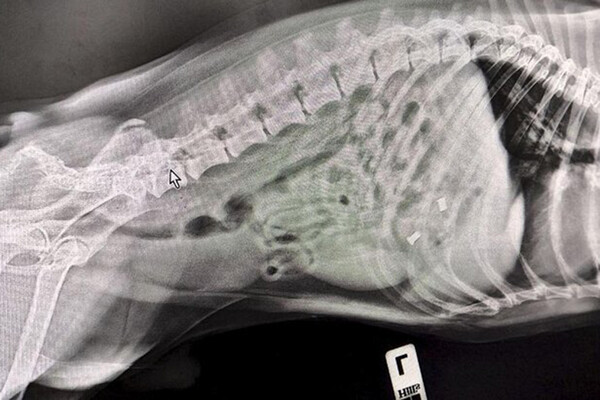

В пресс-службе ведомства уточнили, что владельцы привели к ветеринарам питомца по кличке Смайл с подозрением, что он съел игрушечного дракона. Терапевт Алексей Щукин и УЗ-диагност Елена Сухарева провели УЗИ и рентген. В ходе исследований стало понятно, что внутри собаки находится не один предмет.

«Поскольку Смайла доставили в ветклинику сразу же после происшествия, обошлось без операции. Специалисты вызвали медикаментозную рвоту и удалили предметы из желудка собаки», – отметили в пресс-службе.

Специалисты извлекли из Смайла кусок игрушки и итальянские серьги из муранского стекла. После этого его отпустили домой.